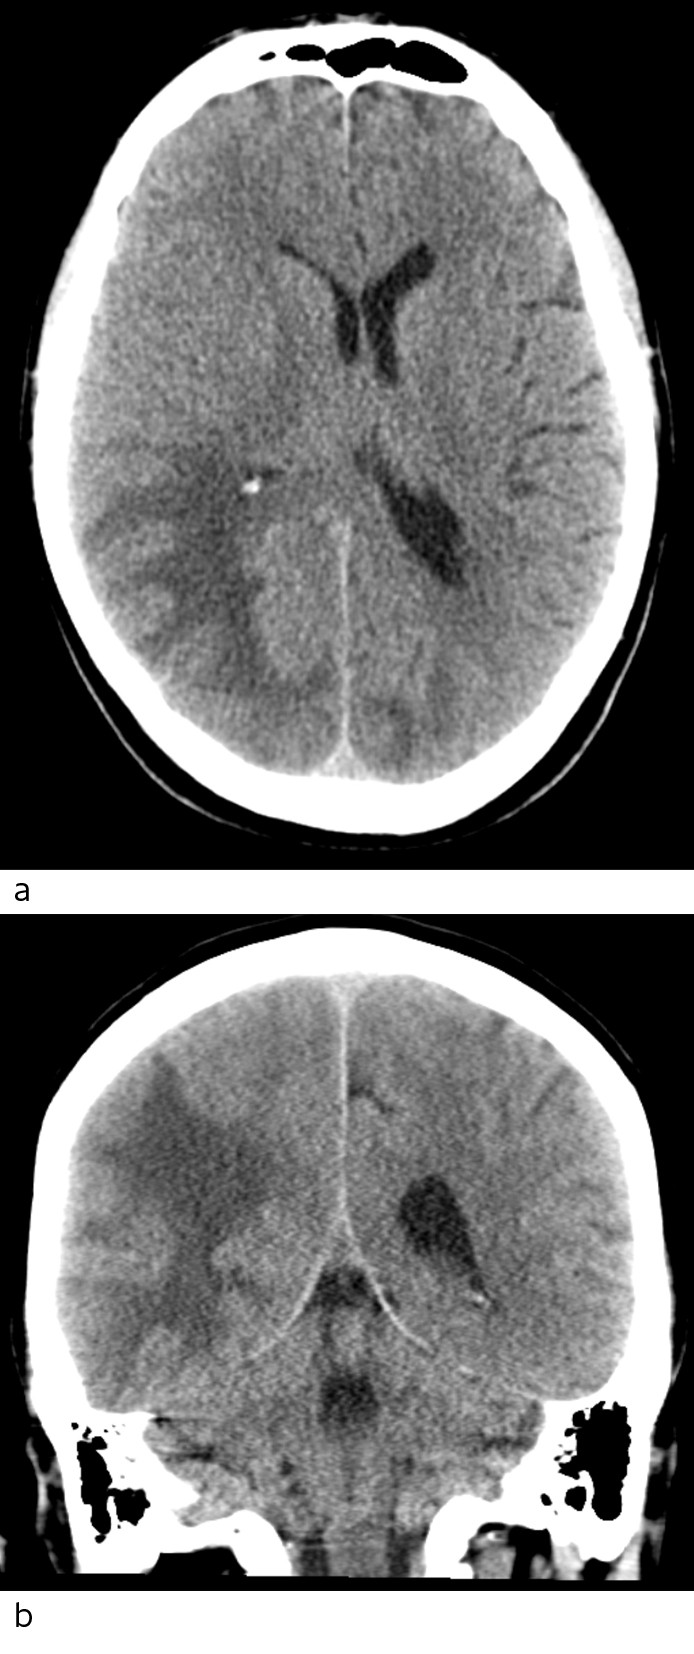

Head CT scans of the patient were taken with and without intravenous contrast. Low attenuation indicative of oedema in the white matter was seen in the occipitotemporal regions, being more pronounced on the right side with a mass effect and displacement of the midline towards the left (Fig. 1).

Figure 1 Head CT scan axial section (a) and coronal section (b) show extensive low-density changes that may be consistent…

Figure 1 Head CT scan axial section (a) and coronal section (b) show extensive low-density changes that may be consistent with oedema occipitotemporally on the right side and occipitally on the left side. No haemorrhaging is seen.